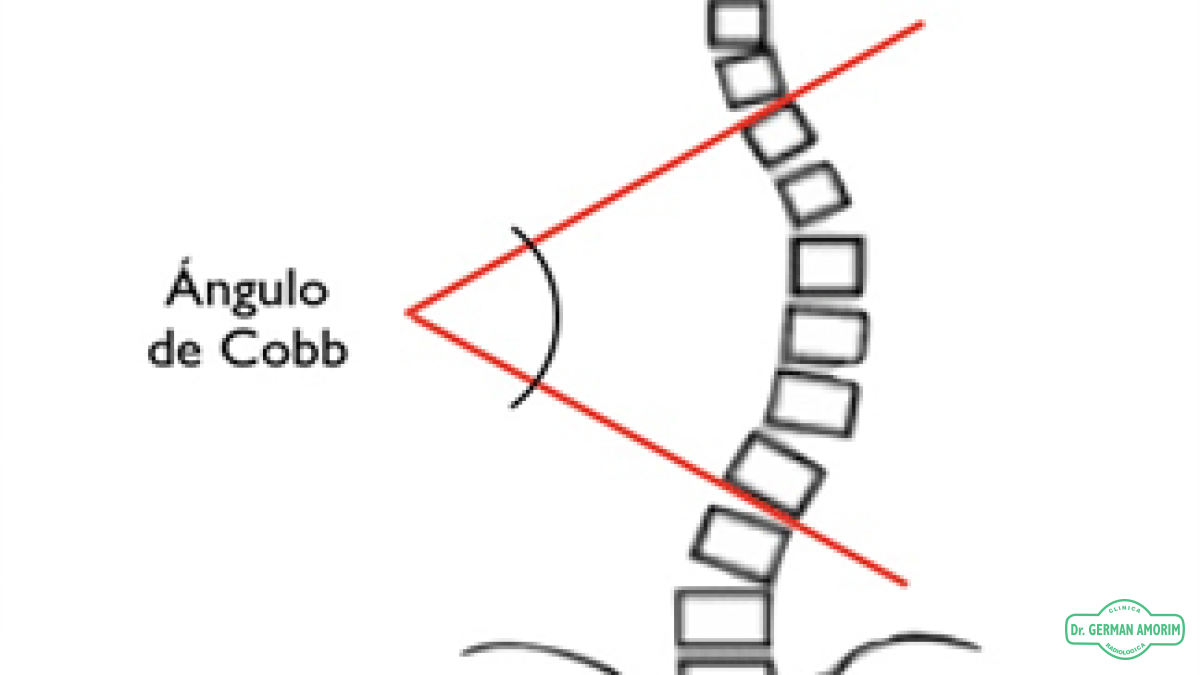

Actualmente se realizan espinogramas digitales que permiten de manera informática medir la alineación y los ángulos de las curvaturas de la columna tanto normales como patológicas.

Esta mediciones múltiples muestra con mayor exactitud los ángulos de Cobb.